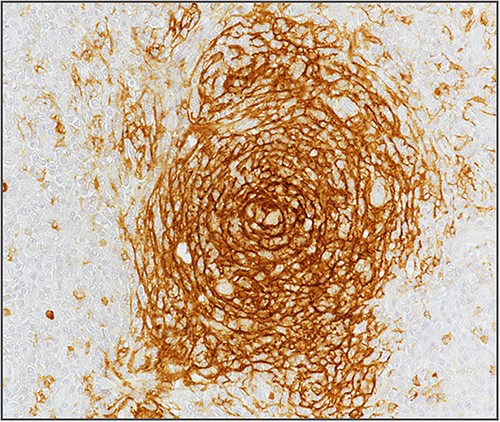

Blood investigations including hematological and biochemical tests revealed a low lymphocytes count with a consequent increased neutrophils percentage, and an increased protein C reactive (PCR) value. Oncological markers were normal. He was also tested for HIV infection, HHV-8, and Epstein–Barr virus with negative results. Positron emission tomography (PET) was performed with evidence of increased metabolic activity at the site of the mass. A suspicious diagnosis of Schwannoma or liposarcoma was made. The patient underwent CT-guided percutaneous biopsy with extemporary histological diagnosis of hyaline-vascular variant Castleman disease. The patient was subdue to laparoscopic removal of the mass. The mass was located near the duodenum without other structures involvement, from which it was isolated and entirely resected comprehending the intact capsule. No intra- and post-operative complications were recorded. The microscopic examination revealed the presence of a single lymph node measuring 7 × 5 × 4.5 cm with clear margins and an architecture characterized by the presence of small follicles distributed over the entire surface, lacking clear centers and polarization (primary follicle or atrophic follicle type), some with prominent vascularization and fibrosis (hyaline-vascular transformation), hyperplasia of the CD21+ follicular dendritic cells (Figs 3 and 4), and a “target” arrangement of the mantle lymphocytes. Large follicles with hyperplastic germinative centers and follicles with small centers duplicate germinatives, marked paracortical interfollicular vascular hyperplasia, and poor polytypic interfollicular plasmacytosis with very low proportion of IgG4+ plasma cells, coexist (Fig. 5).

Hyperplasia of follicular dendritic cells (staining of follicular dendritic cells with anti-CD21 antibody).